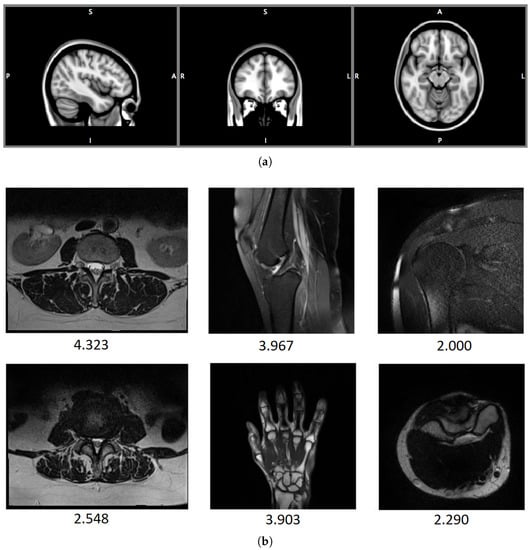

| DB1 | 2020 | 70 | marosz.kia.prz.edu.pl/ENMIQA.html |

| DB2 | 2020 | 240 | marosz.kia.prz.edu.pl/NOMRIQA.html |